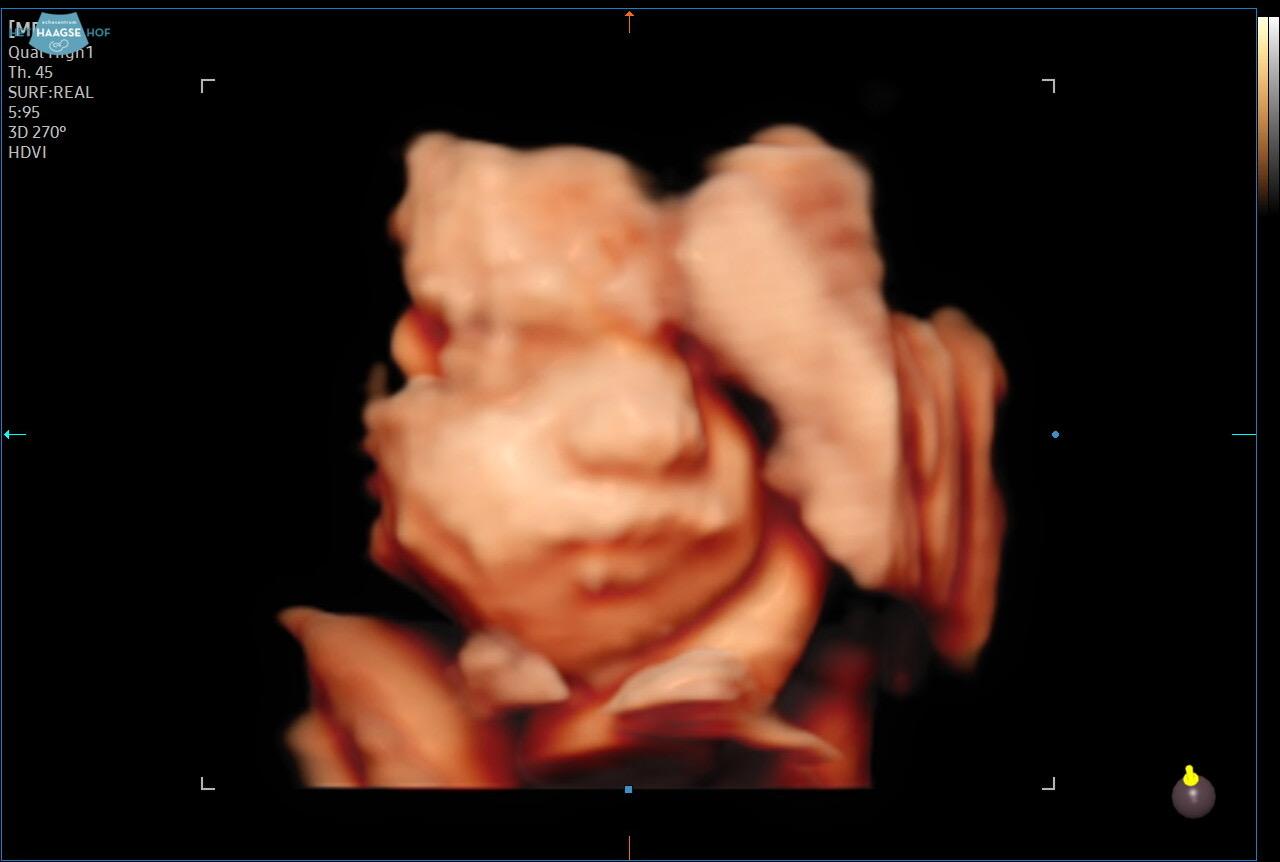

Vanochtend vroeg opgestaan. In mijn hmc zie ik dat mijn bericht van vrijdag nog niet gelezen is . Ik besluit om 9.15 zelf te gaan bellen. De assistente zegt we hebben een bericht over je gekregen . Ze dacht dat ik opgenomen was geweest . Nee dus , mijn radioloog is er vandaag niet 😬 maar ik wil gewoon iemand spreken want zo wil ik niet verder ! Ik krijg een bel afspraak met de dienstdoende radioloog. Om iets voor half 1 wordt ik gebeld . Een fijn gesprek gehad ze snapt dat ik er helemaal doorheen zit . En dat ik me beroerd voel . Ze zegt dat wanneer ze mij naar haar toe laat komen ik mijn afspraak met de kno arts mis en dat dat niet verstandig is . Wanneer ik niet geholpen wordt adviseert ze mij om haar terug te bellen . Om 14.20 heb ik in het Westeinde ziekenhuis een afspraak met de kno arts . Het spreekuur loopt iets uit . Ik heb het koud dus zit daar in mijn jas in de wachtkamer 🫢 eindelijk wordt ik geroepen. Hij gaat eerst in gesprek hoe het gaat . Het gaat niet goed met mij voel me echt beroerd . Kan bijna niet plassen . Dan wil hij toch eerst even met een camera kijken . Hij zegt weinig maar wil mij ipv over 6 maanden  over 2 maanden zien . ( over drie maanden heb ik weer een afspraak bij de radioloog en dan dus over 6 maanden weer bij de kno arts) hij wil dat ik even mijn urine laat testen of ik niet ook een blaasontsteking heb. Ik denk zelf van niet maargoed prima . Ik hoop alleen dat ik er iets uit krijg. Dan zegt hij zie je het zitten tot woensdag te wachten tot je bij de MDL arts moet komen . Ik zeg nee sorry ik wil niet meer tot woensdag wachten voel me echt niet goed . Dan besluit hij gelijk de oncologie kno verpleegkundige te roepen om toch gelijk een sonde te plaatsen. Angela neemt mij mee naar een andere kamer waar ze de sonde plaatst . Ze probeert maagsap op te trekken via de sonde maar er komt niks .mogelijk omdat ik heb gevraagd de sonde wat dieper te leggen . De sonde gaat er wat lastig in omdat alles uitgedroogd is . Maar het lukt .Ze vraagt of ik bezwaar heb als ze langs de sonde met een scoop kijkt of de sonde goed in de maag ligt ik zeg probeer maar . Ze doet de scoop langs de sonde want helaas is er bij mij maar een neusgat toegankelijk . De sonde ligt goed in de maag dus ik hoef niet ook nog Eén röntgen foto te laten maken om te kijken of de sonde goed zit . Dan ga ik proberen mijn urine in te leveren . Het lukt om 20 ml te plassen hopelijk is dat genoeg ! Onderweg naar Lisa bedenk ik mij oeps vergeten een nieuwe afspraak te maken over 2 maanden .ik loop woensdag wel even langs . Lisa is met Don voor een 3 D echo een paar straten verderop . Omdat de kleine meid niet mee wil werken . Kan ik onverwachts er toch bij zijn . Toch nog wat leuks vandaag . Mooie beelden krijgen we te zien . Nog 10 weekjes geduld en dan kunnen we haar snel in het echt zien .